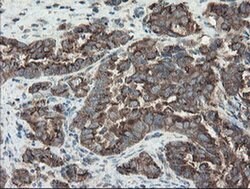

ACBD3 Monoclonal Antibody for Western Blot, IHC (P), Flow

| Flow Cytometry, Immunohistochemistry (Paraffin), Western Blot | |